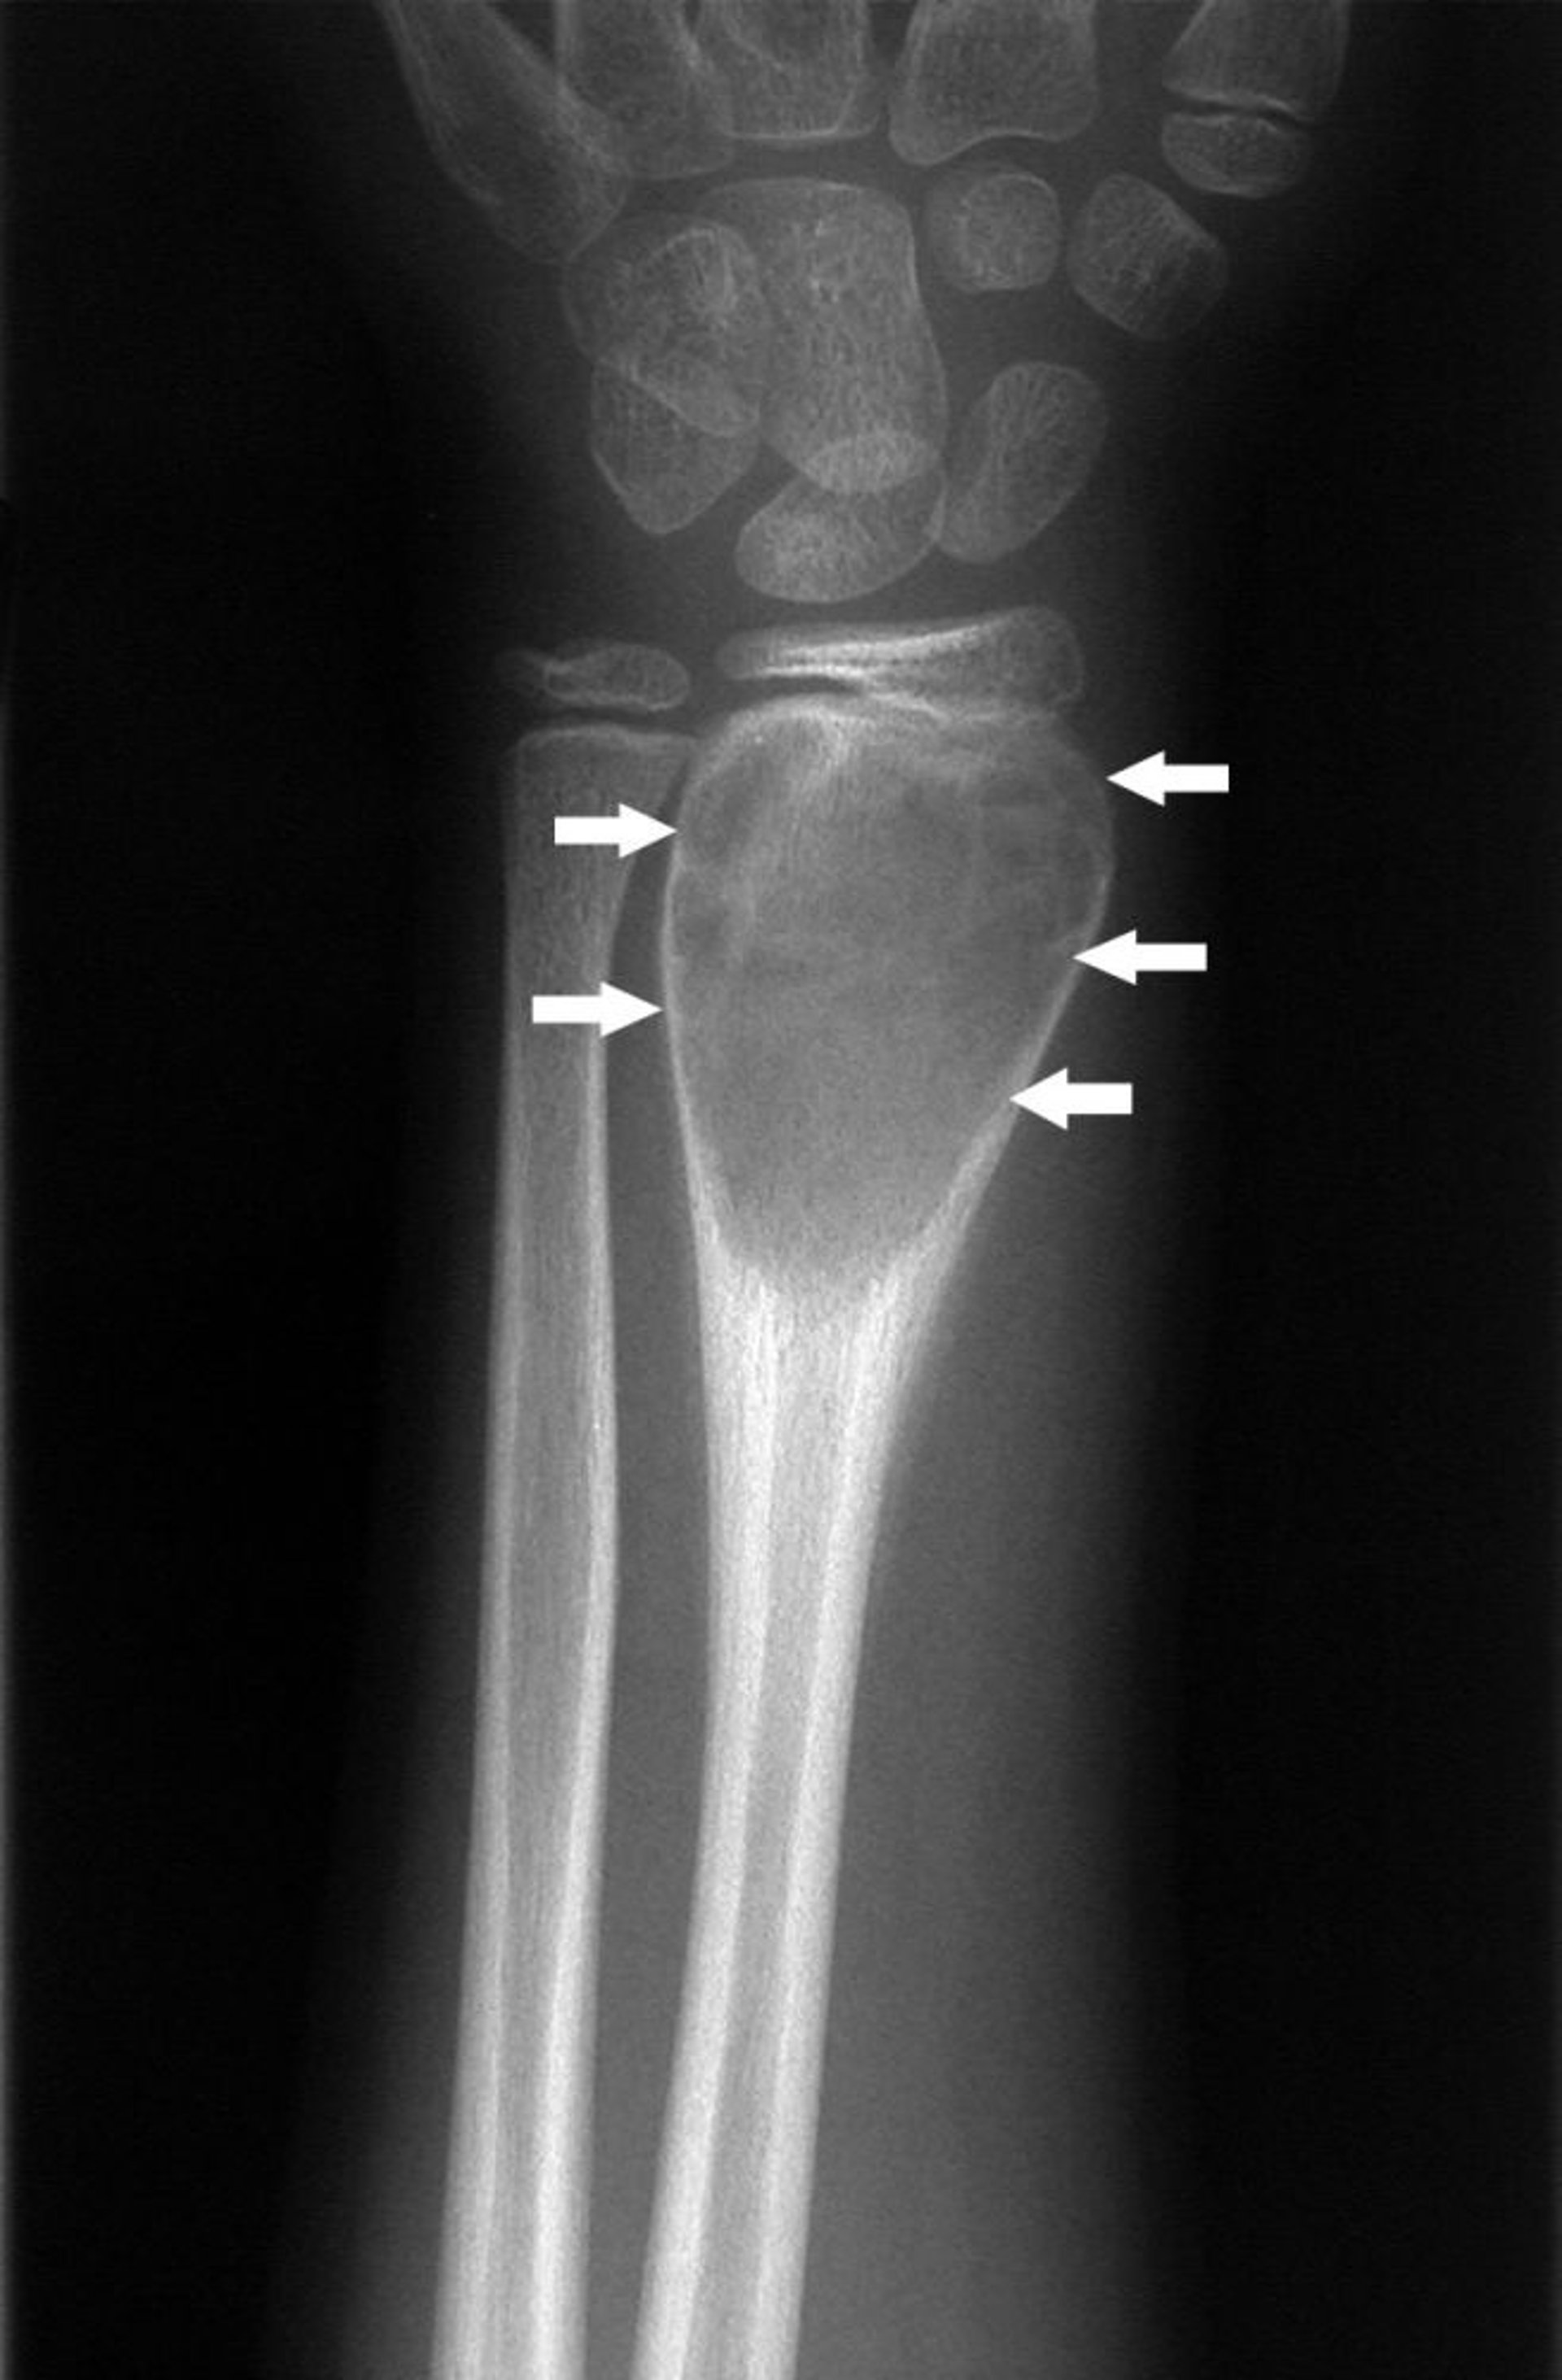

कलाई का यह एक्स-रे एक हड्डी के एन्युरिज़्मल सिस्ट (तीर) को दिखाता है।

मिशेल जे. जॉयस, MD, और हैकन इलास्लैन MD के छवि सौजन्य से।